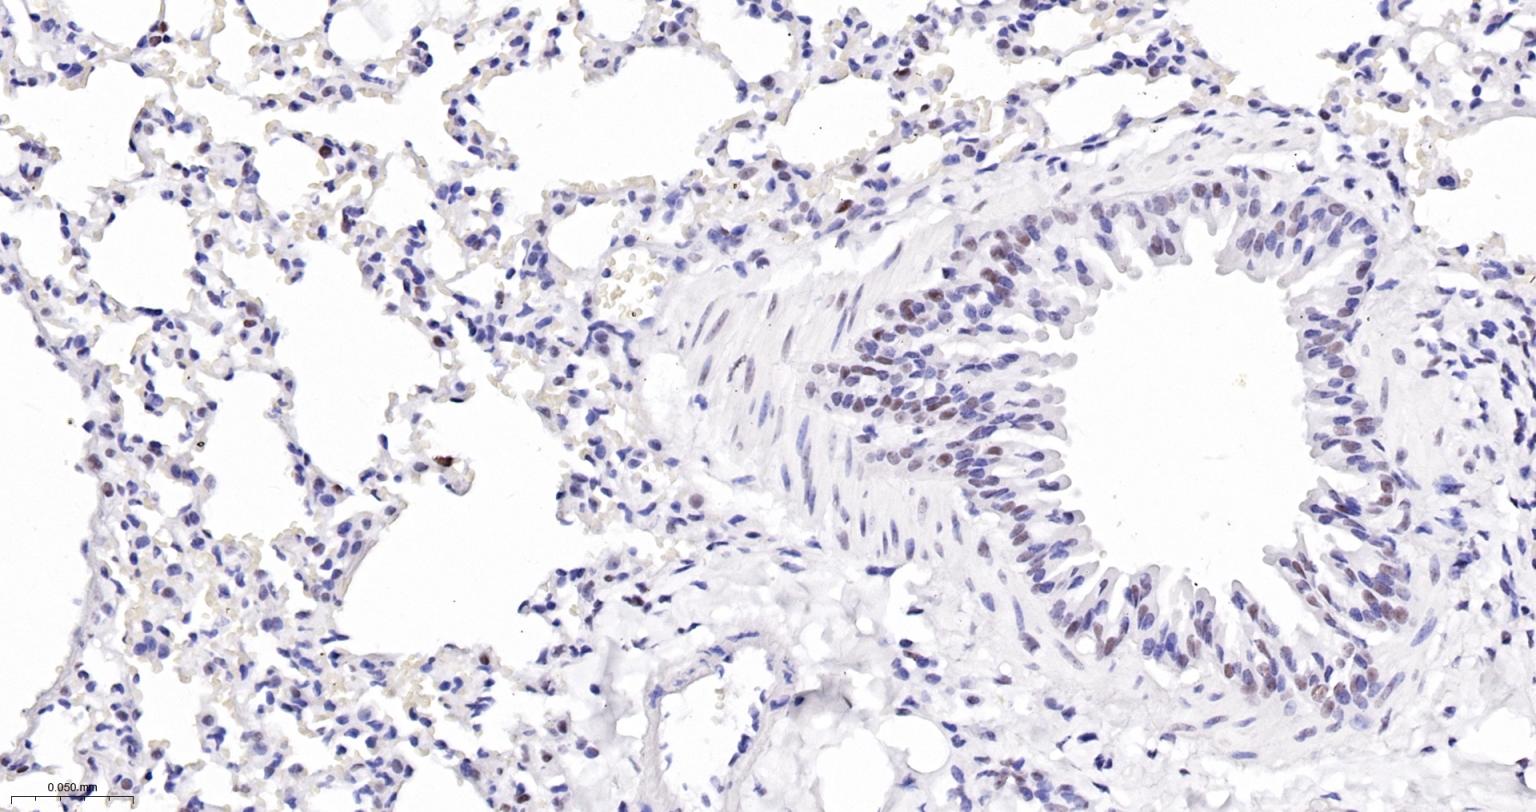

Paraformaldehyde-fixed, paraffin embedded Mouse Lung; Antigen retrieval by boiling in sodium citrate buffer (pH6.0) for 15 min; The section was incubated with USP39 Monoclonal Antibody, Unconjugated (bsm-63016R) at 1:200 overnight at 4°C, followed by conjugation to the bs-0295G-HRP and DAB (C-0010) staining.